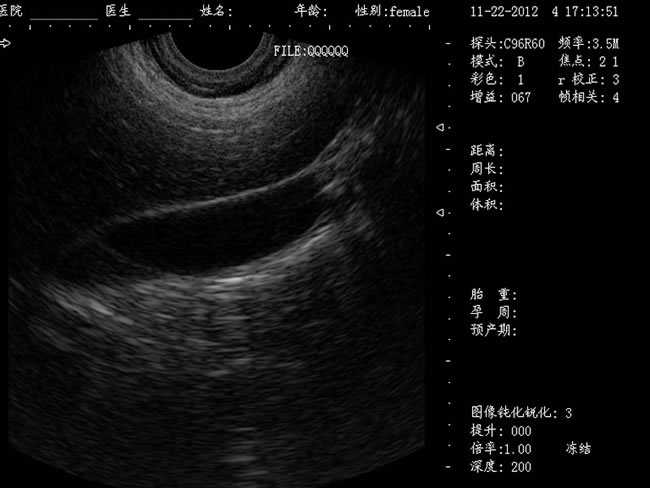

婦產科手術監視儀-可視人流機掃描角度:

b) 3.5MHz凸陣探頭:60º可視可調;